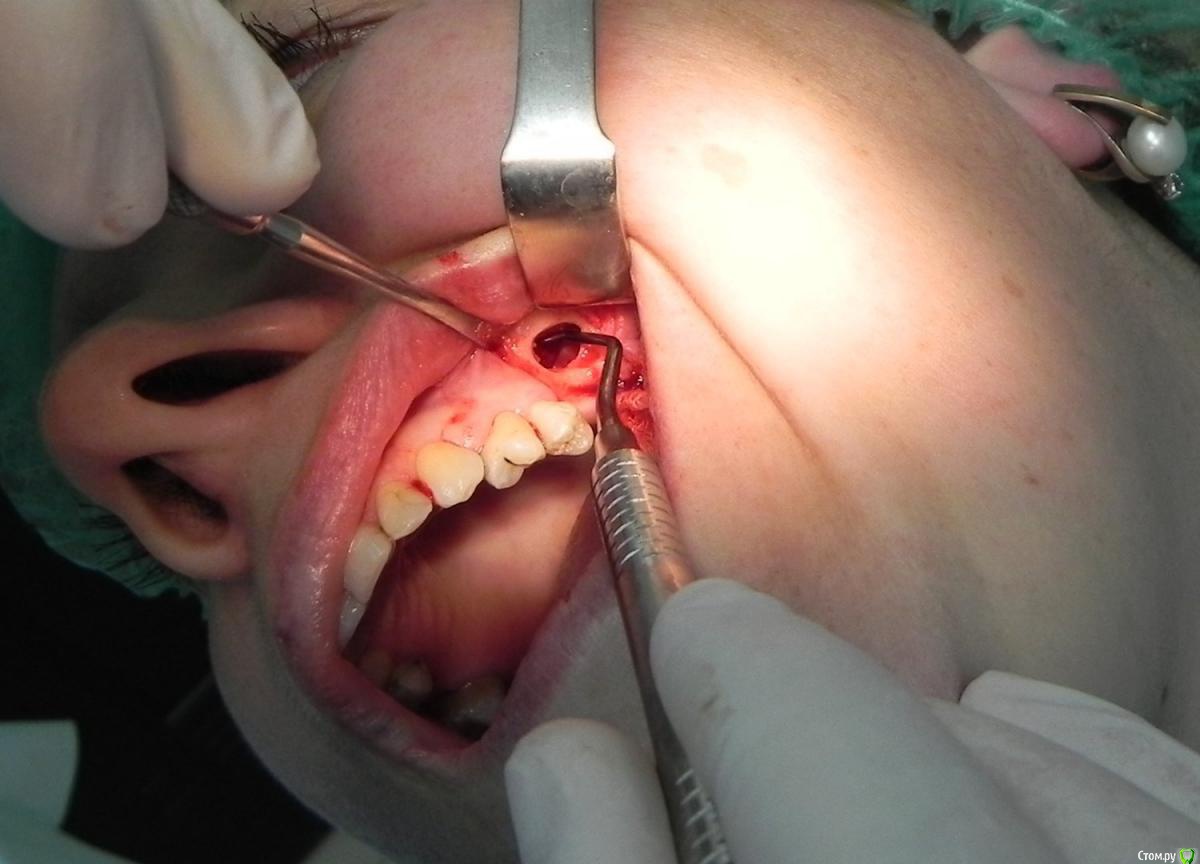

Kostoprav Опубликовано 7 августа, 2015 Поделиться Опубликовано 7 августа, 2015 доступпрепаровка шаровидной костной фрезойпри отслаивании мембраны образовалась маленькая перфа перфорацию" проклеил" коллагеновой мембранойпод мембрану внесен материалмембрана на окноготово может кому из начинающих этот пост полезен будет 1 Ссылка на комментарий

Jurai Опубликовано 7 августа, 2015 Поделиться Опубликовано 7 августа, 2015 что это между швами? дренаж? а зачем? 5 Ссылка на комментарий

Kostoprav Опубликовано 7 августа, 2015 Автор Поделиться Опубликовано 7 августа, 2015 что это между швами? дренаж? а зачем?там вообще то не один а два, второй за зубом спрятался) профилактика гематомы, я их на следующий день или два убираю Ссылка на комментарий

Популярный пост carloss Опубликовано 7 августа, 2015 Популярный пост Поделиться Опубликовано 7 августа, 2015 то есть возможность инфицирования графта через щель для дренажа исключается? 20 Ссылка на комментарий

Kostoprav Опубликовано 8 августа, 2015 Автор Поделиться Опубликовано 8 августа, 2015 то есть возможность инфицирования графта через щель для дренажа исключается?не думаю что инфекция проникнет через щель от дренажа учитывая то что дренаж удаляется через сутки и пациент принимает антибиотики, во всяком случае у меня такого не было тьфу-тьфу Ссылка на комментарий